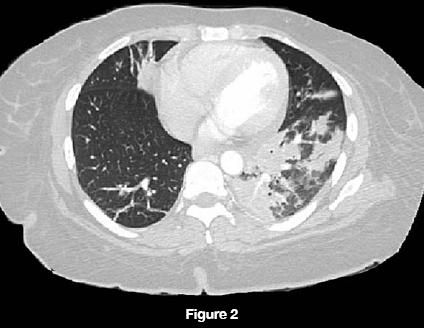

The patient's chest radiograph revealed left lower lobe, lingular, and right upper lobe infiltrates (Figure 1). A CT scan of the chest revealed 2.8-cm right hilar adenopathy and 2.0-cm left hilar adenopathy with patchy areas of consolidation in the right upper, right middle, left lower, and lingular lobes (Figure 2).

The most common presentation of Nocardia infection involves pulmonary manifestations, which are seen in more than two thirds of cases.3 The radiographic appearance is protean. Parenchymal disease may include irregular nodules (with large nodules usually cavitating), reticulonodular or diffuse pneumonic infiltrates, and pleural effusions. The pneumonic infiltrates are necrotizing and poorly contained, resulting in erosion into bony structures. The radiological findings may be similar to those of tuberculosis-upper lobe cavitary infiltrates are commonly seen.